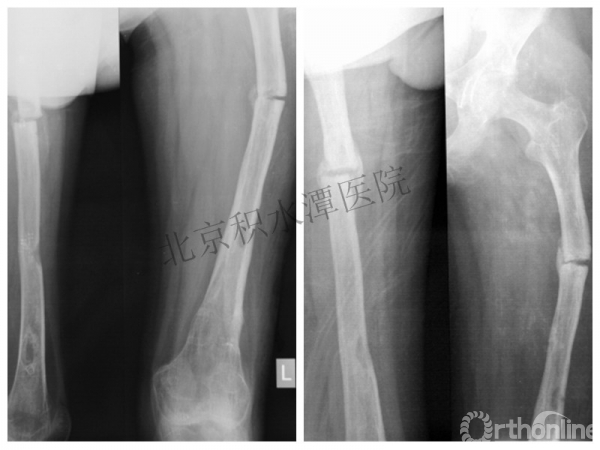

病例分享三

男孩、9岁,滑雪受伤,胫腓骨螺旋形骨折(粉碎性)

这个病例郭教授在积水潭医院骨科高研班时多次讲到,也在互动交流中惊人地看到,了解到现实之令人难以想象!

手法整复,石膏制动!

整复后7天

儿童具备强大的愈合潜力,同样也有极强的塑形能力

某种情况下,The best treatment is no treatment! 最佳治疗反而是不治疗!因为很多骨折依靠儿童强大的塑形能力和特点完全可以得到满意的结果!